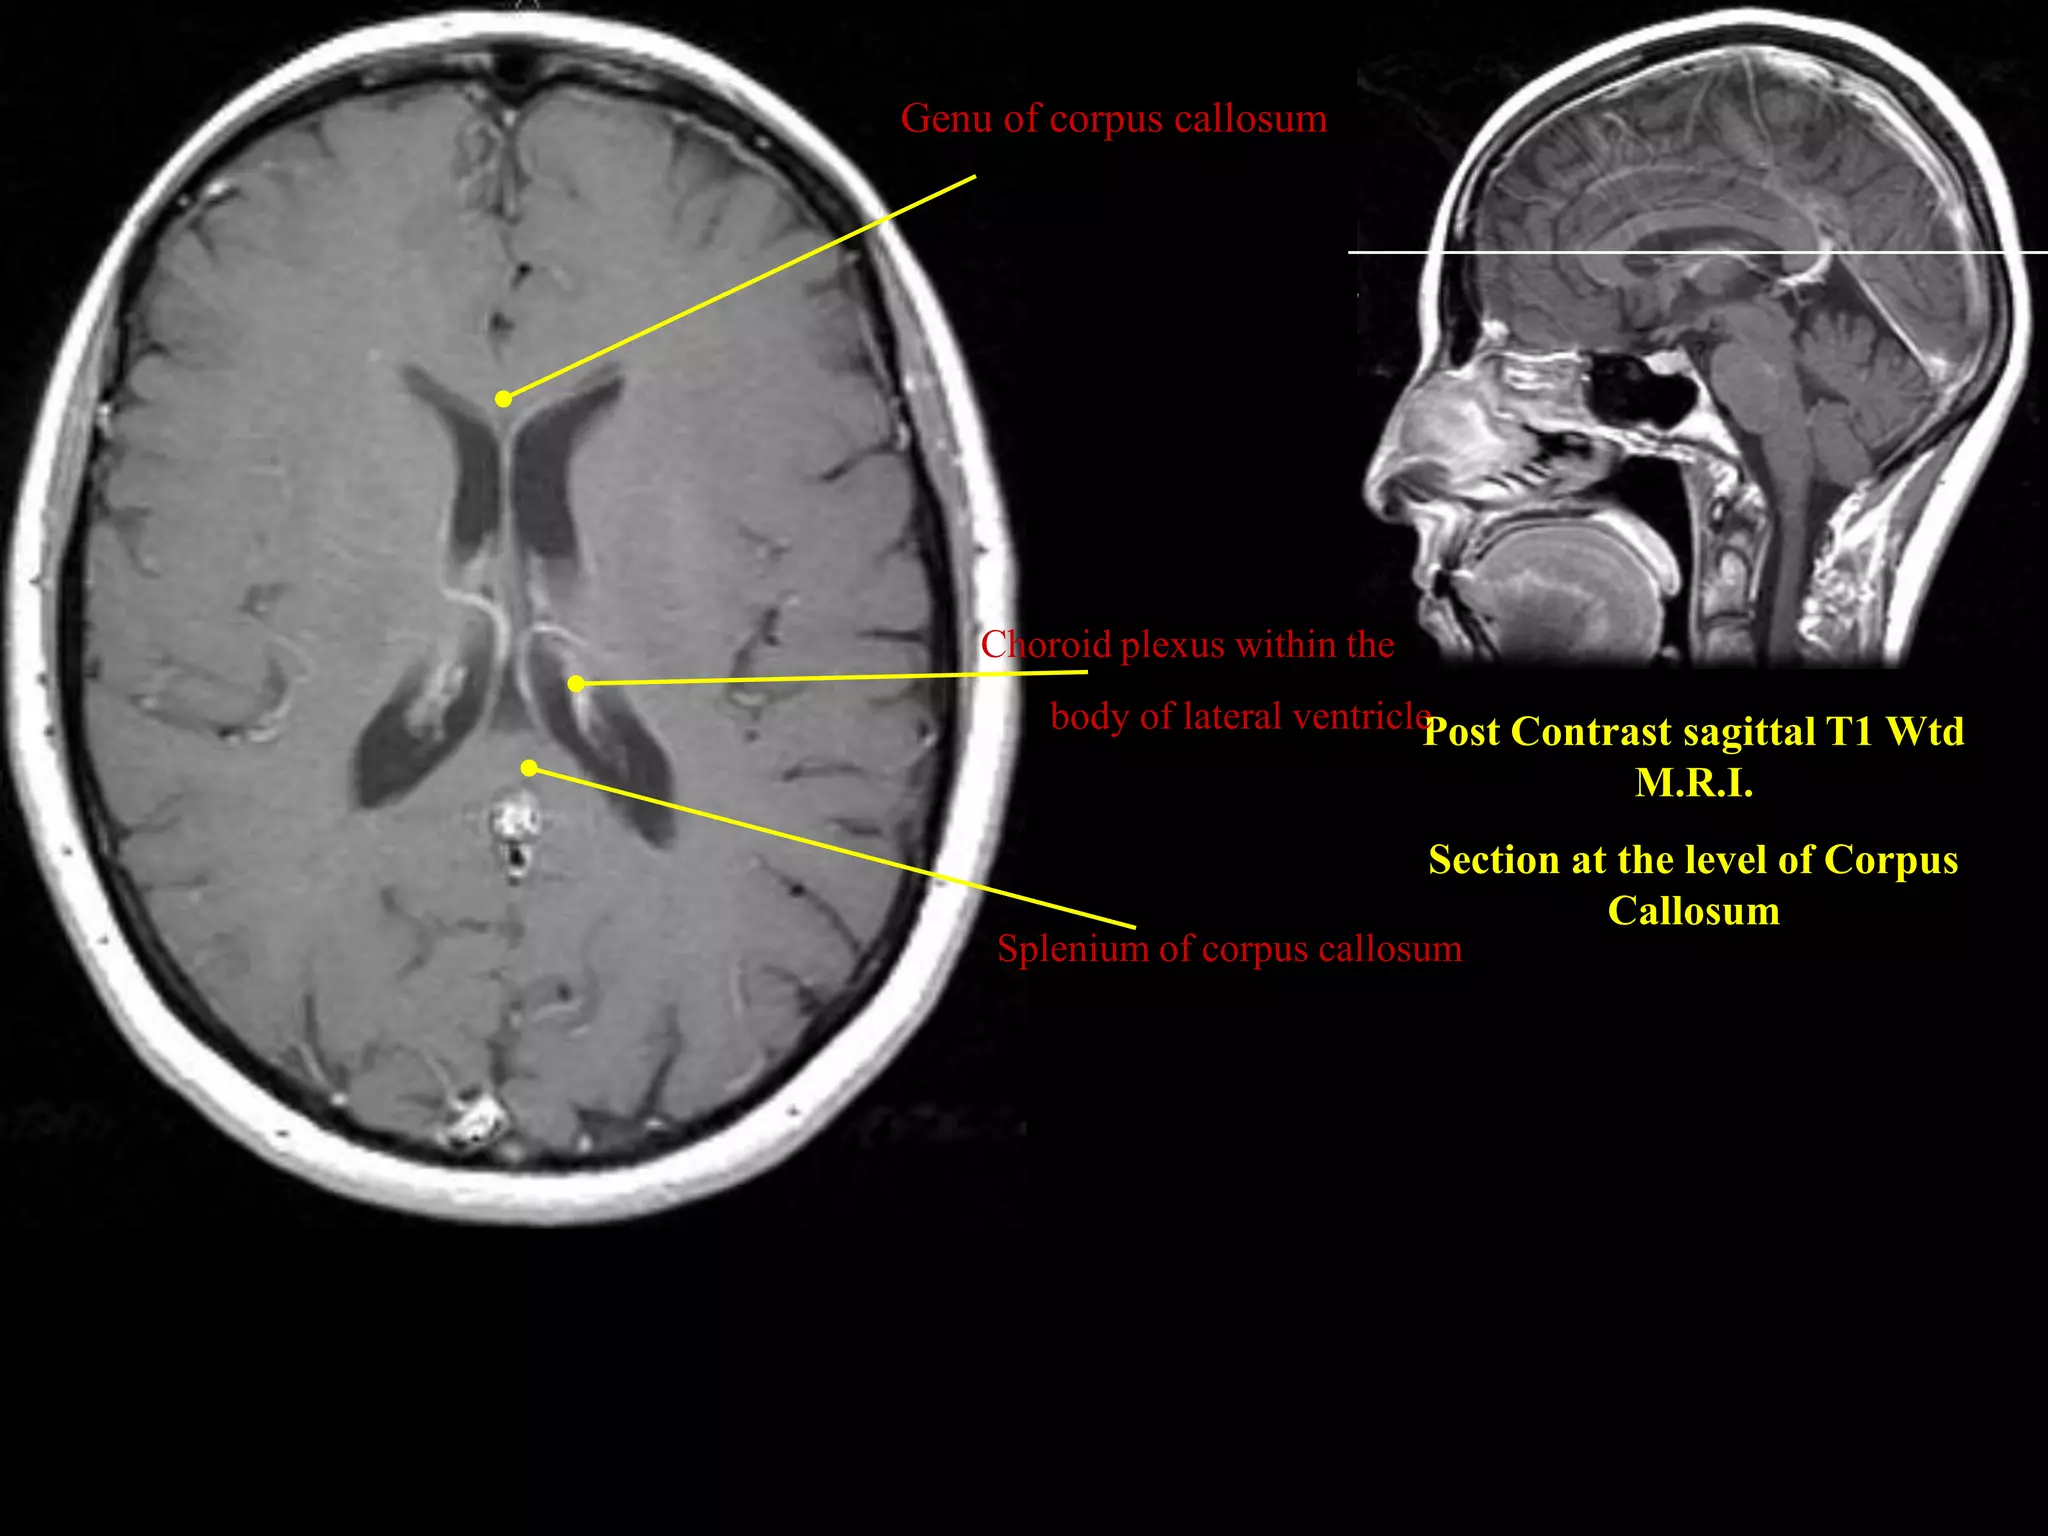

MRI SECTIONAL ANATOMY OF BRAIN | PPTX